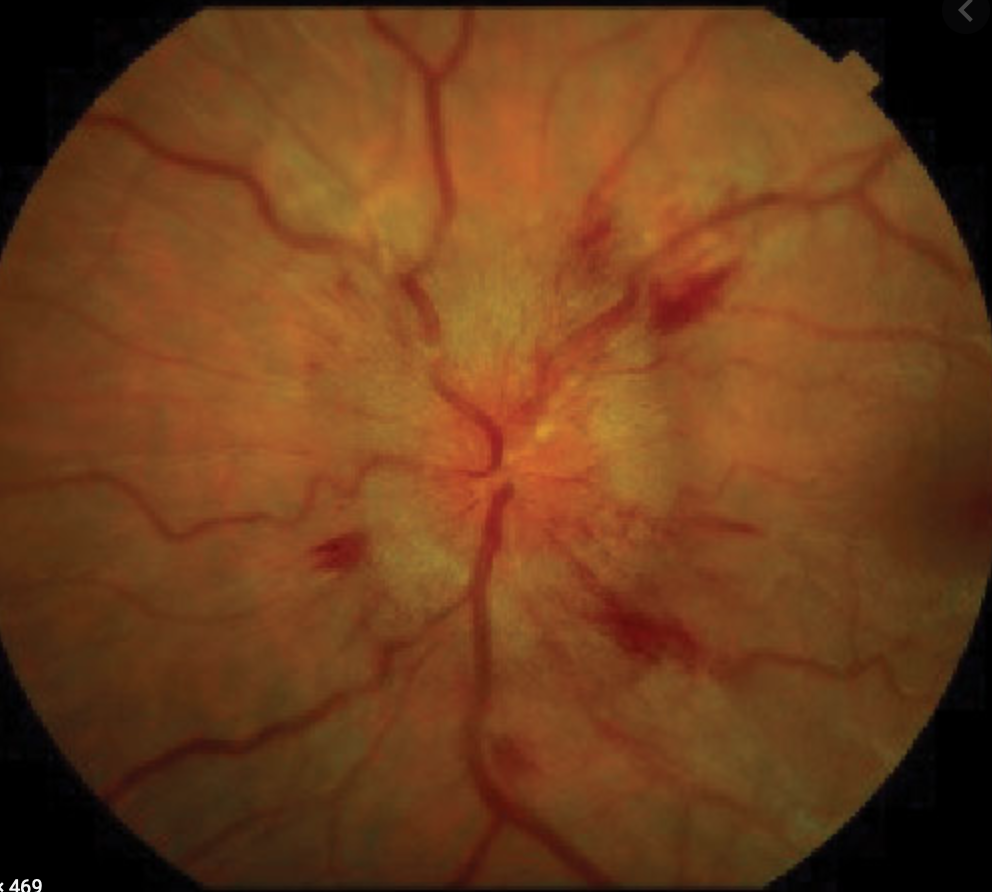

Central Vein Occlusion